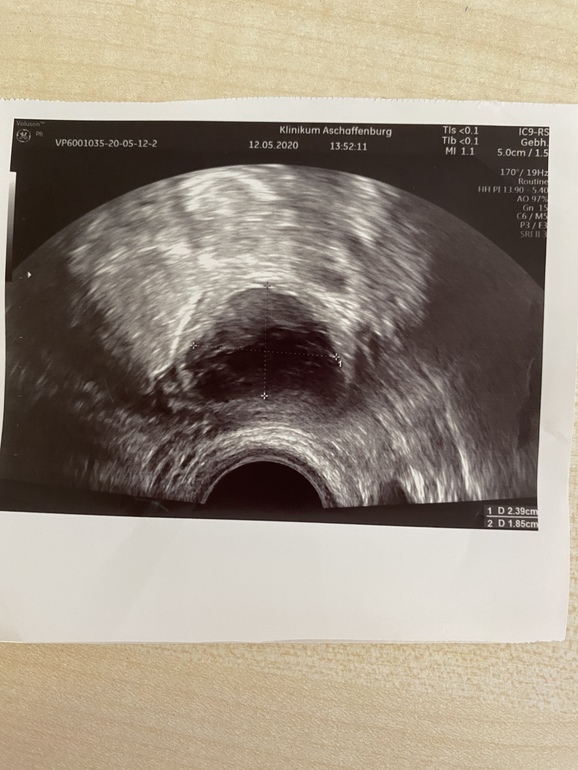

Желтое тело на 7 ДПО

Ждем дня Х (Признаки беременности / Тесты)Всем привет на 7 ДПО желтое тело такое странное типа с кровоизлиянием.

Сказали точно не киста. Стенки не ровные . Размер 2,3х1,8

Говорят О скорей всего была.